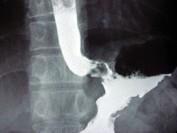

问题 男,56岁,胸骨后不适3个月,吞咽时有异物感,X线检查如图,最可能的诊断是 ( )

选项 A.食管癌 B.食管腺瘤 C.贲门腺癌 D.胃癌 E.食管下段溃疡

答案 C